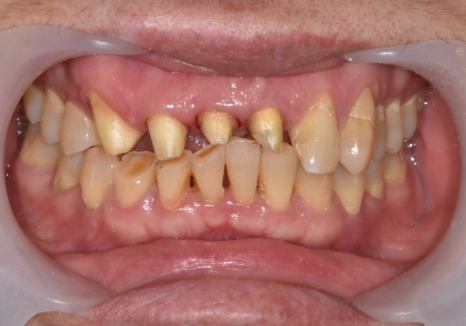

이 환자분은

오래전 위 앞니 4개를

보철로 씌우셨는데,

시간이 흐르면서

심미적으로나 기능적으로

문제가 생긴 상태였습니다.

입안을 자세히 살펴보니

원인은 크게 세 가지였습니다.

유독 길게 제작된 위 앞니가

아랫니를 계속 건드리면서,

아랫니 속살(상아질)이 비칠 만큼

심하게 마모되어 있었습니다.

아랫니가 닳아 키가 작아지다 보니,

상대적으로 윗니는 더 들쑥날쑥하고

삐뚤어 보일 수밖에 없었죠.

잇몸이 내려가면서

뿌리가 드러나보이고,

보철 안쪽의 금속 테두리가

까맣게 보였습니다.